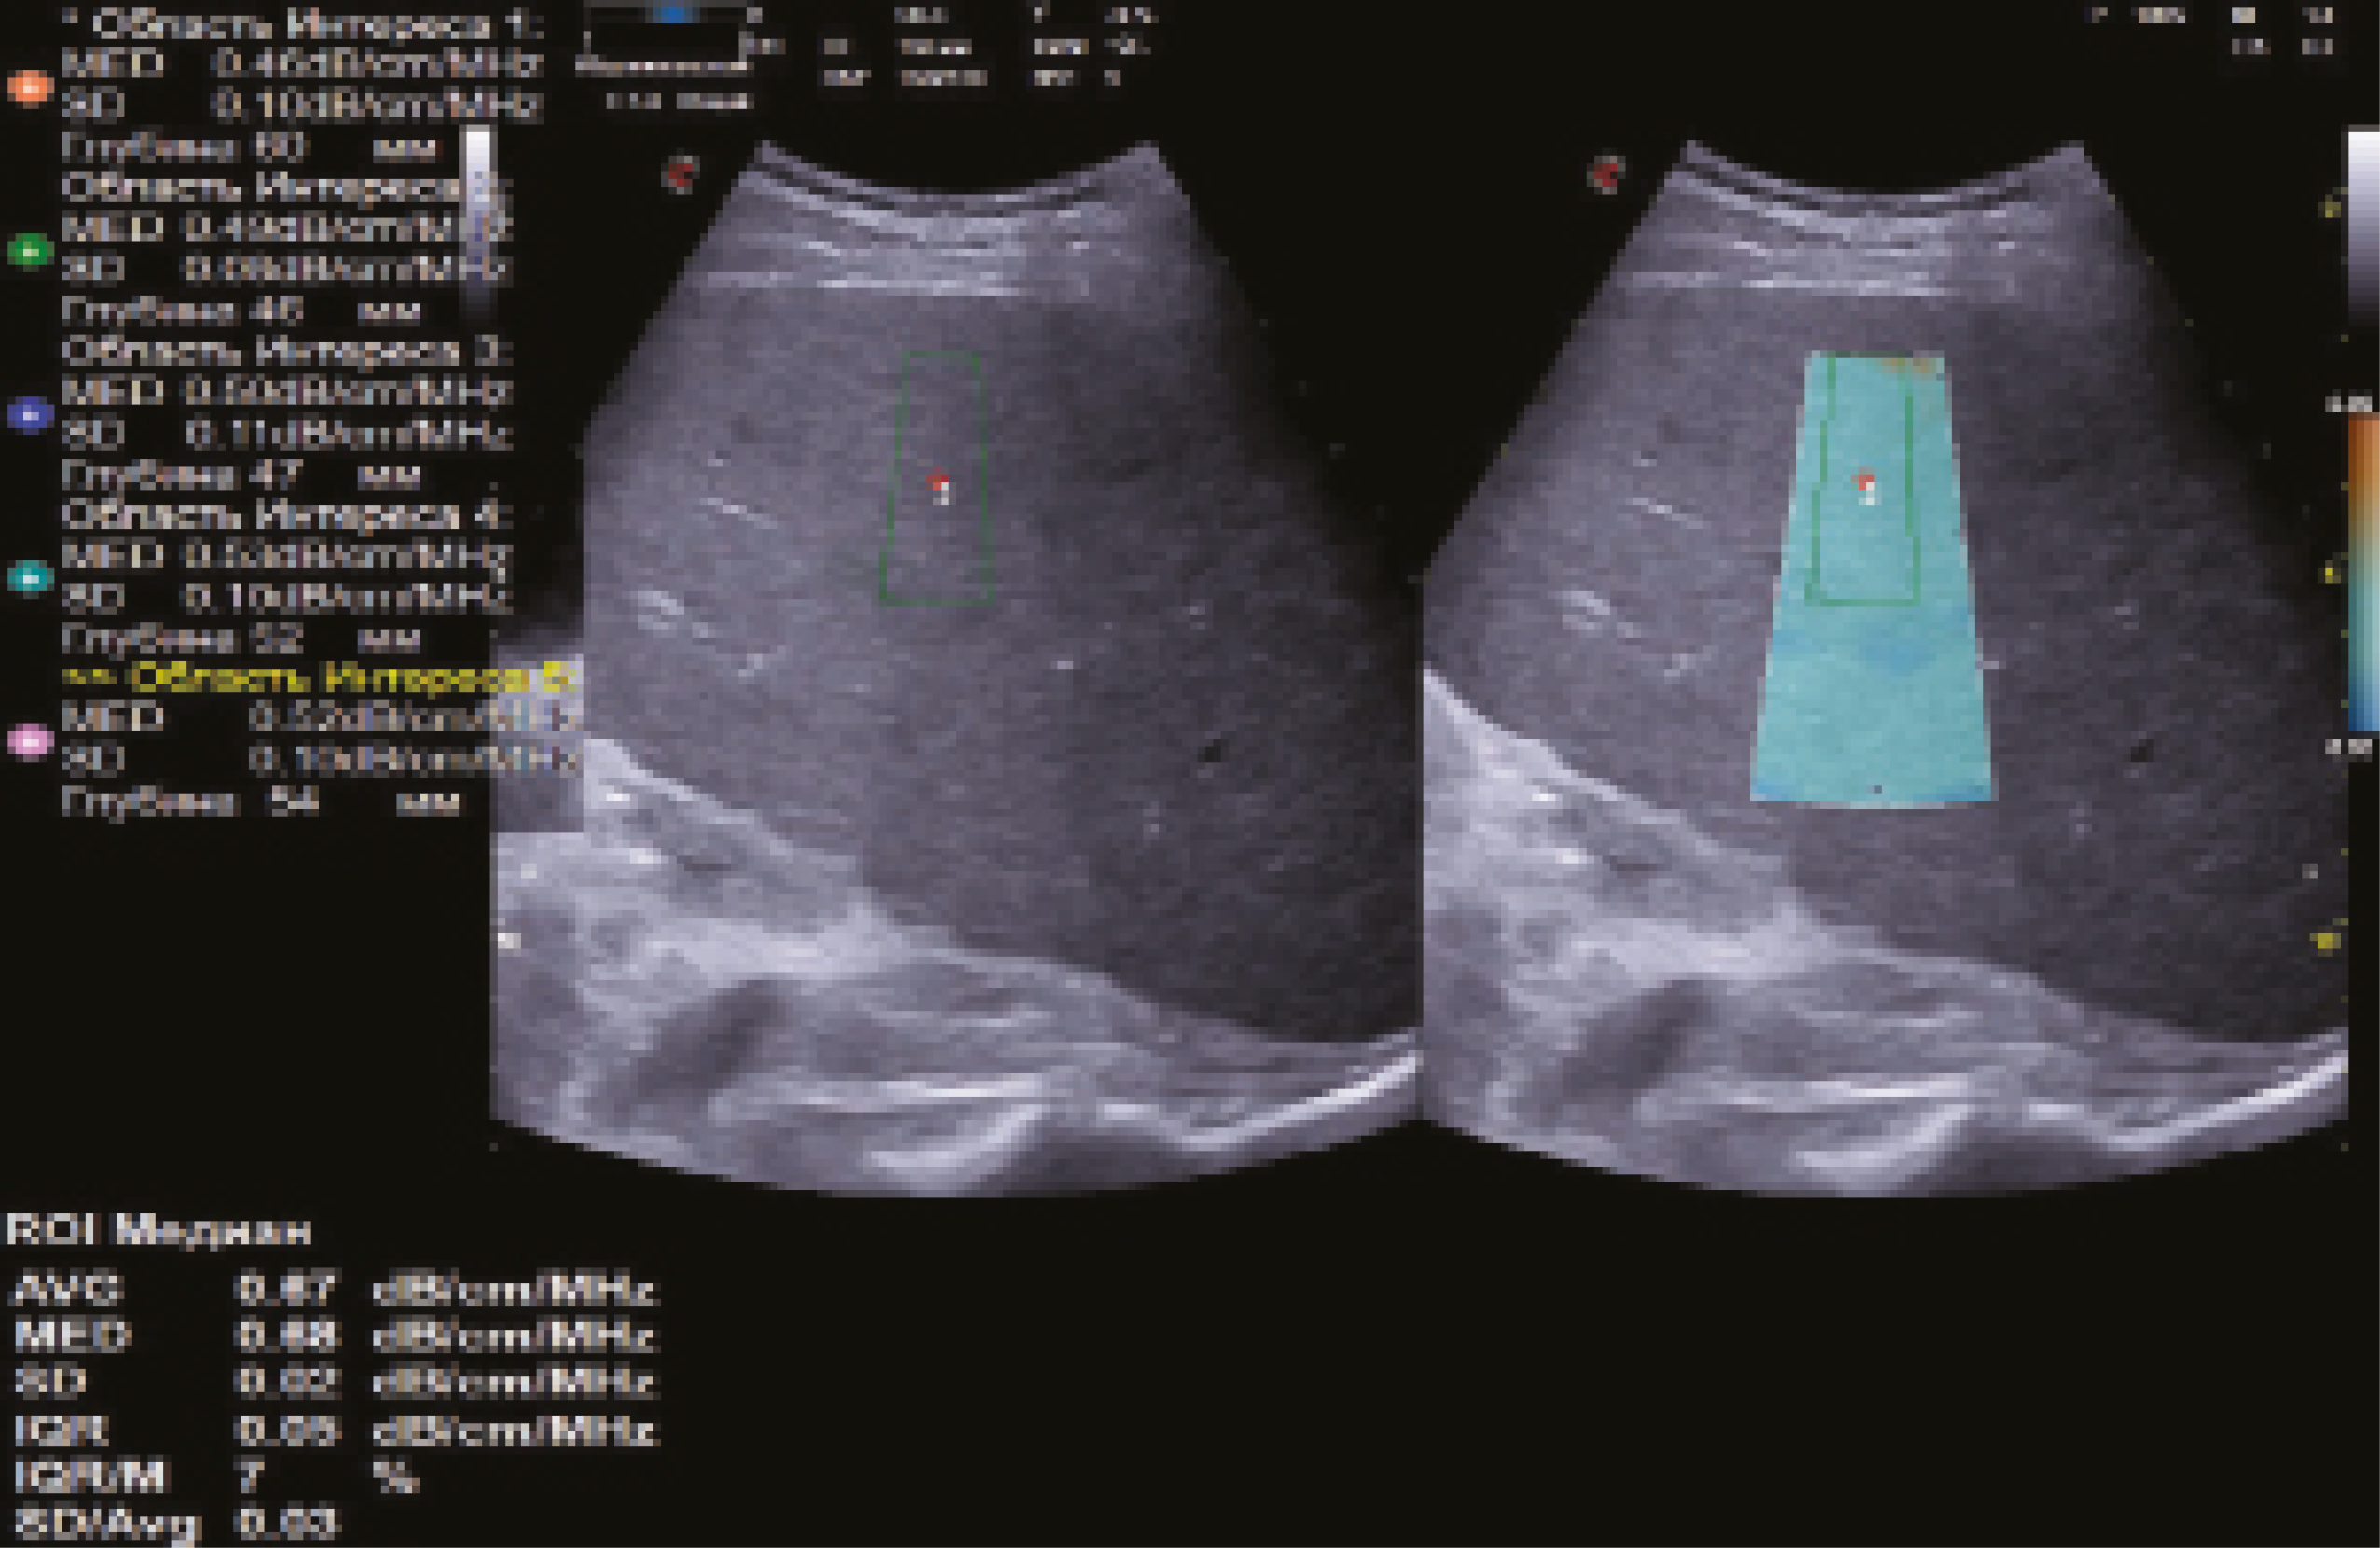

Рис. 9. Эхограмма количественной ультразвуковой стеатометрии печени с определением коэффициента затухания ультразвуковой волны (0,67 дБ/см/МГц, стеатоз печени S1 – минимально выраженный), выполненная по правилам, предложенным авторами